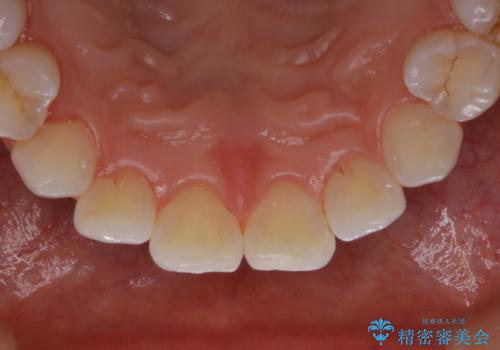

PMTCで見た目を綺麗に

- 専門的な機械ででしっかりとキレイにクリーニングしてほしいとのことでしたPMTC60分コースを行いました。

PMTCは、歯に付着した汚れを除去していくため、着色が気になる場合にも行うことができます。ご自身でのセルフケアだけで着色を落とそうとすると、逆に歯を傷つけてしまったり、精密に汚れを除去できないこともあります。また、日常生活で着色しやすい飲食物を避けたりすることはストレスに感じてしまったり、あまり現実的ではありません。

毎日丁寧に歯磨きをしていても、日常生活での飲食物などにより着色してしまうことはあります。PMTCでは、歯の表面の凸凹にミネラルを補給して、ツルツルの表面に仕上げます